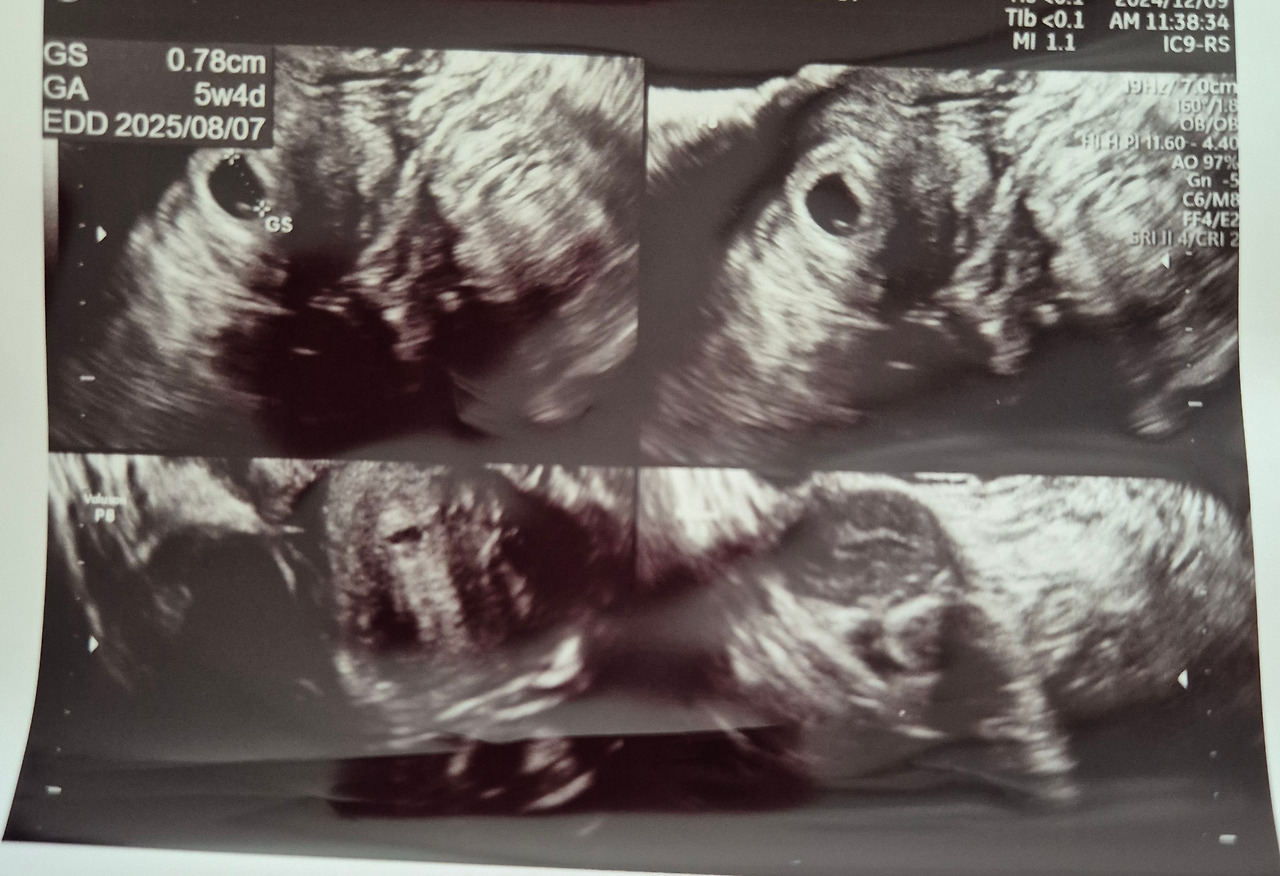

의심스러운 마음으로 병원을 찾았다. 초음파 화면을 보며 의사가 말했다. "아기집이 보이네요." 나는 화면 속 점 하나를 보며 고개를 갸우뚱했다. "그러니까… 진짜 임신이라는 거죠?" 몇 번을 되묻고 나서야 겨우 실감이 났다. 그러니까, 나는 지금 임신 5주 차이고, 내년 8월 8일쯤 아이를 만날 수 있다는 것이다.

주말을 겨우 버티고 월요일에 다시 병원을 찾았다.

다행히 아기집은 거기 그대로 있었다. 아니, 단 5일 만에 크기가 두 배로 커져 있었다.

의사가 초음파 화면에서 생명의 흔적을 하나하나 짚어줄 때마다 마음 한구석이 뜨거워졌다.